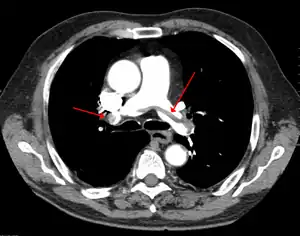

Embolism pulmonar

Embolismul pulmonar (EP) este un tip de embolism, o blocare a arterelor pulmonare, cauzată de migrarea la acest nivel a unei mase dintr-o altă zonă a corpului.[2] Simptomele includ: dispnee, durere toracică și tuse cu sânge.[3] Pot să apară și simptomele unei tromboze venoase profunde la nivelul membrelor inferioare, precum: eritem, căldură, edem și durere.[3] Boala poate să fie acompaniată de valori scăzute ale oxigenului, tahipnee (respirație rapidă), tahicardie (bătăi rapide ale cordului) și uneori de febră/subfebrilitate.[4] Cazurile severe pot duce la sincopă, șoc hipotensiv și moarte subită.[5]